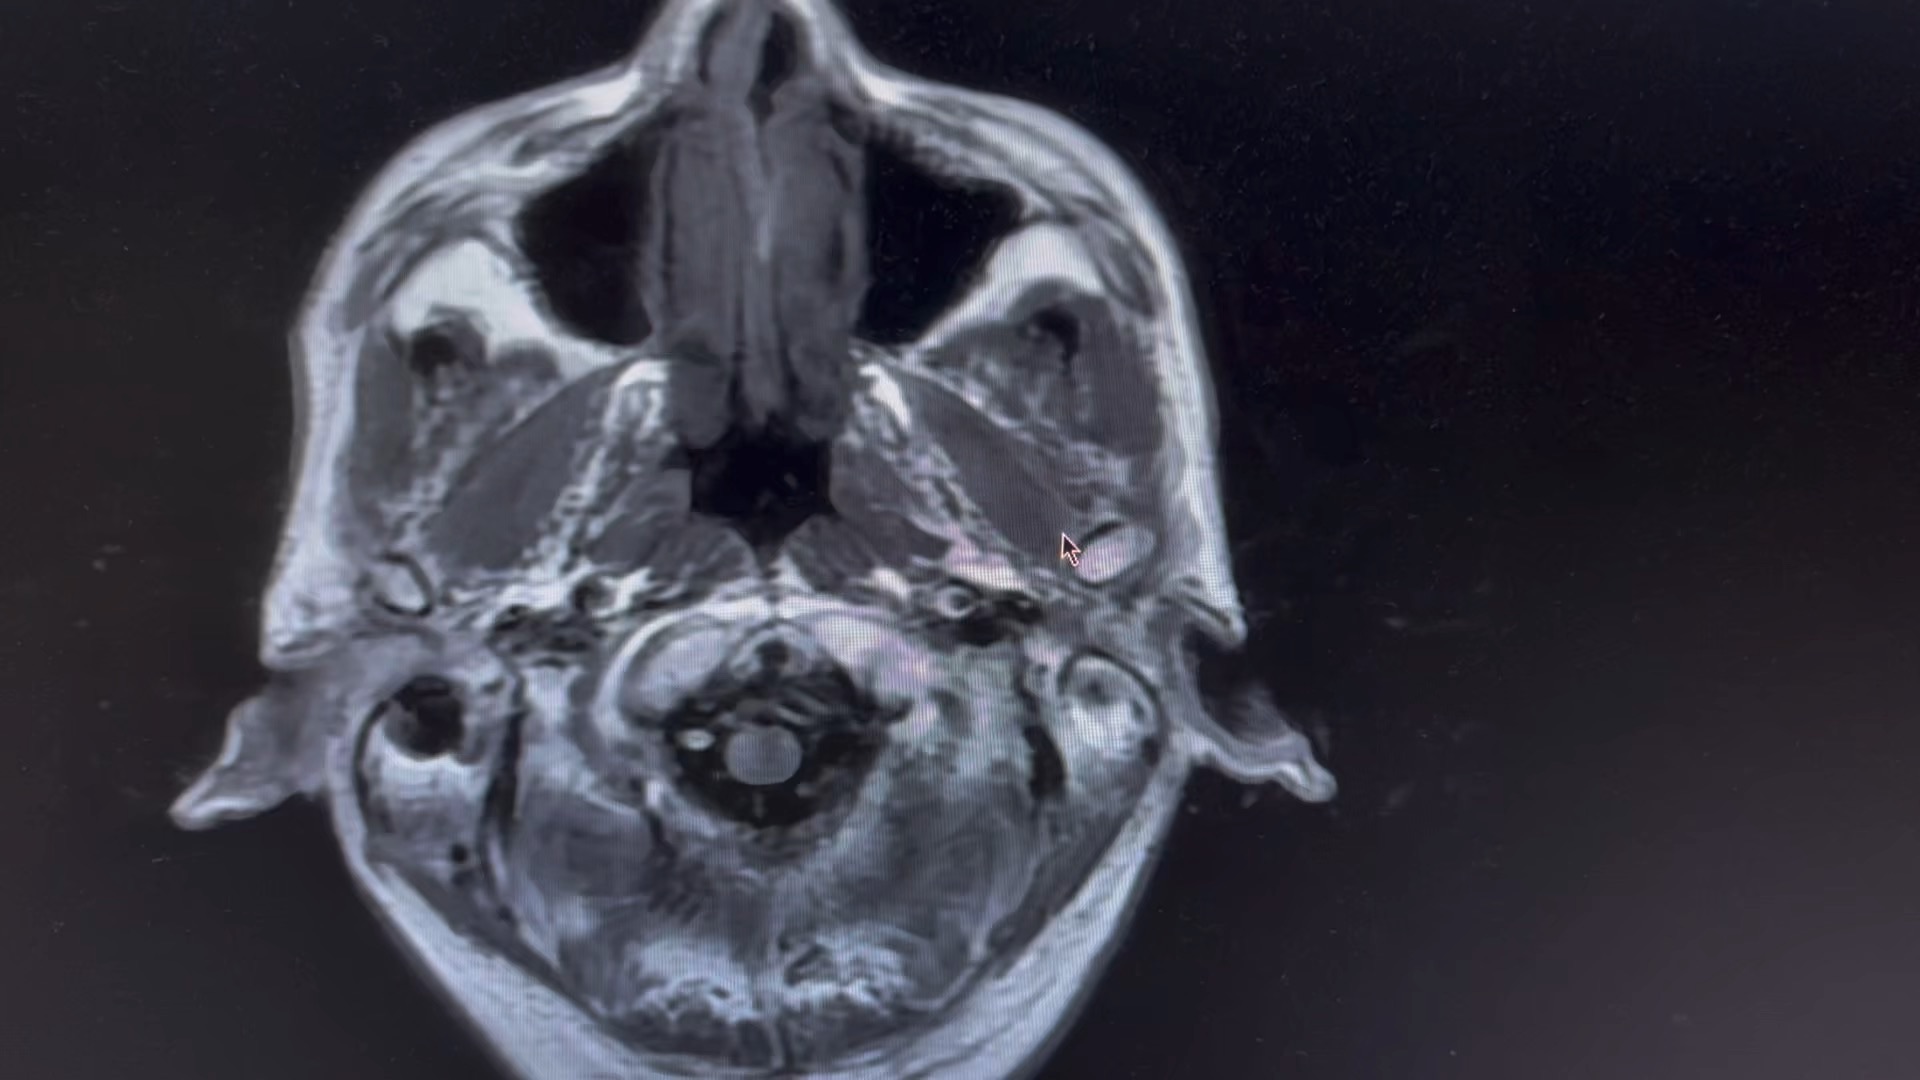

男,66 岁

突发剧烈头疼,呕吐伴意识模糊数小时。

一人在家,家属下班后发现患者情况不对,拨打 120 急诊入院,已转入脑介入科。